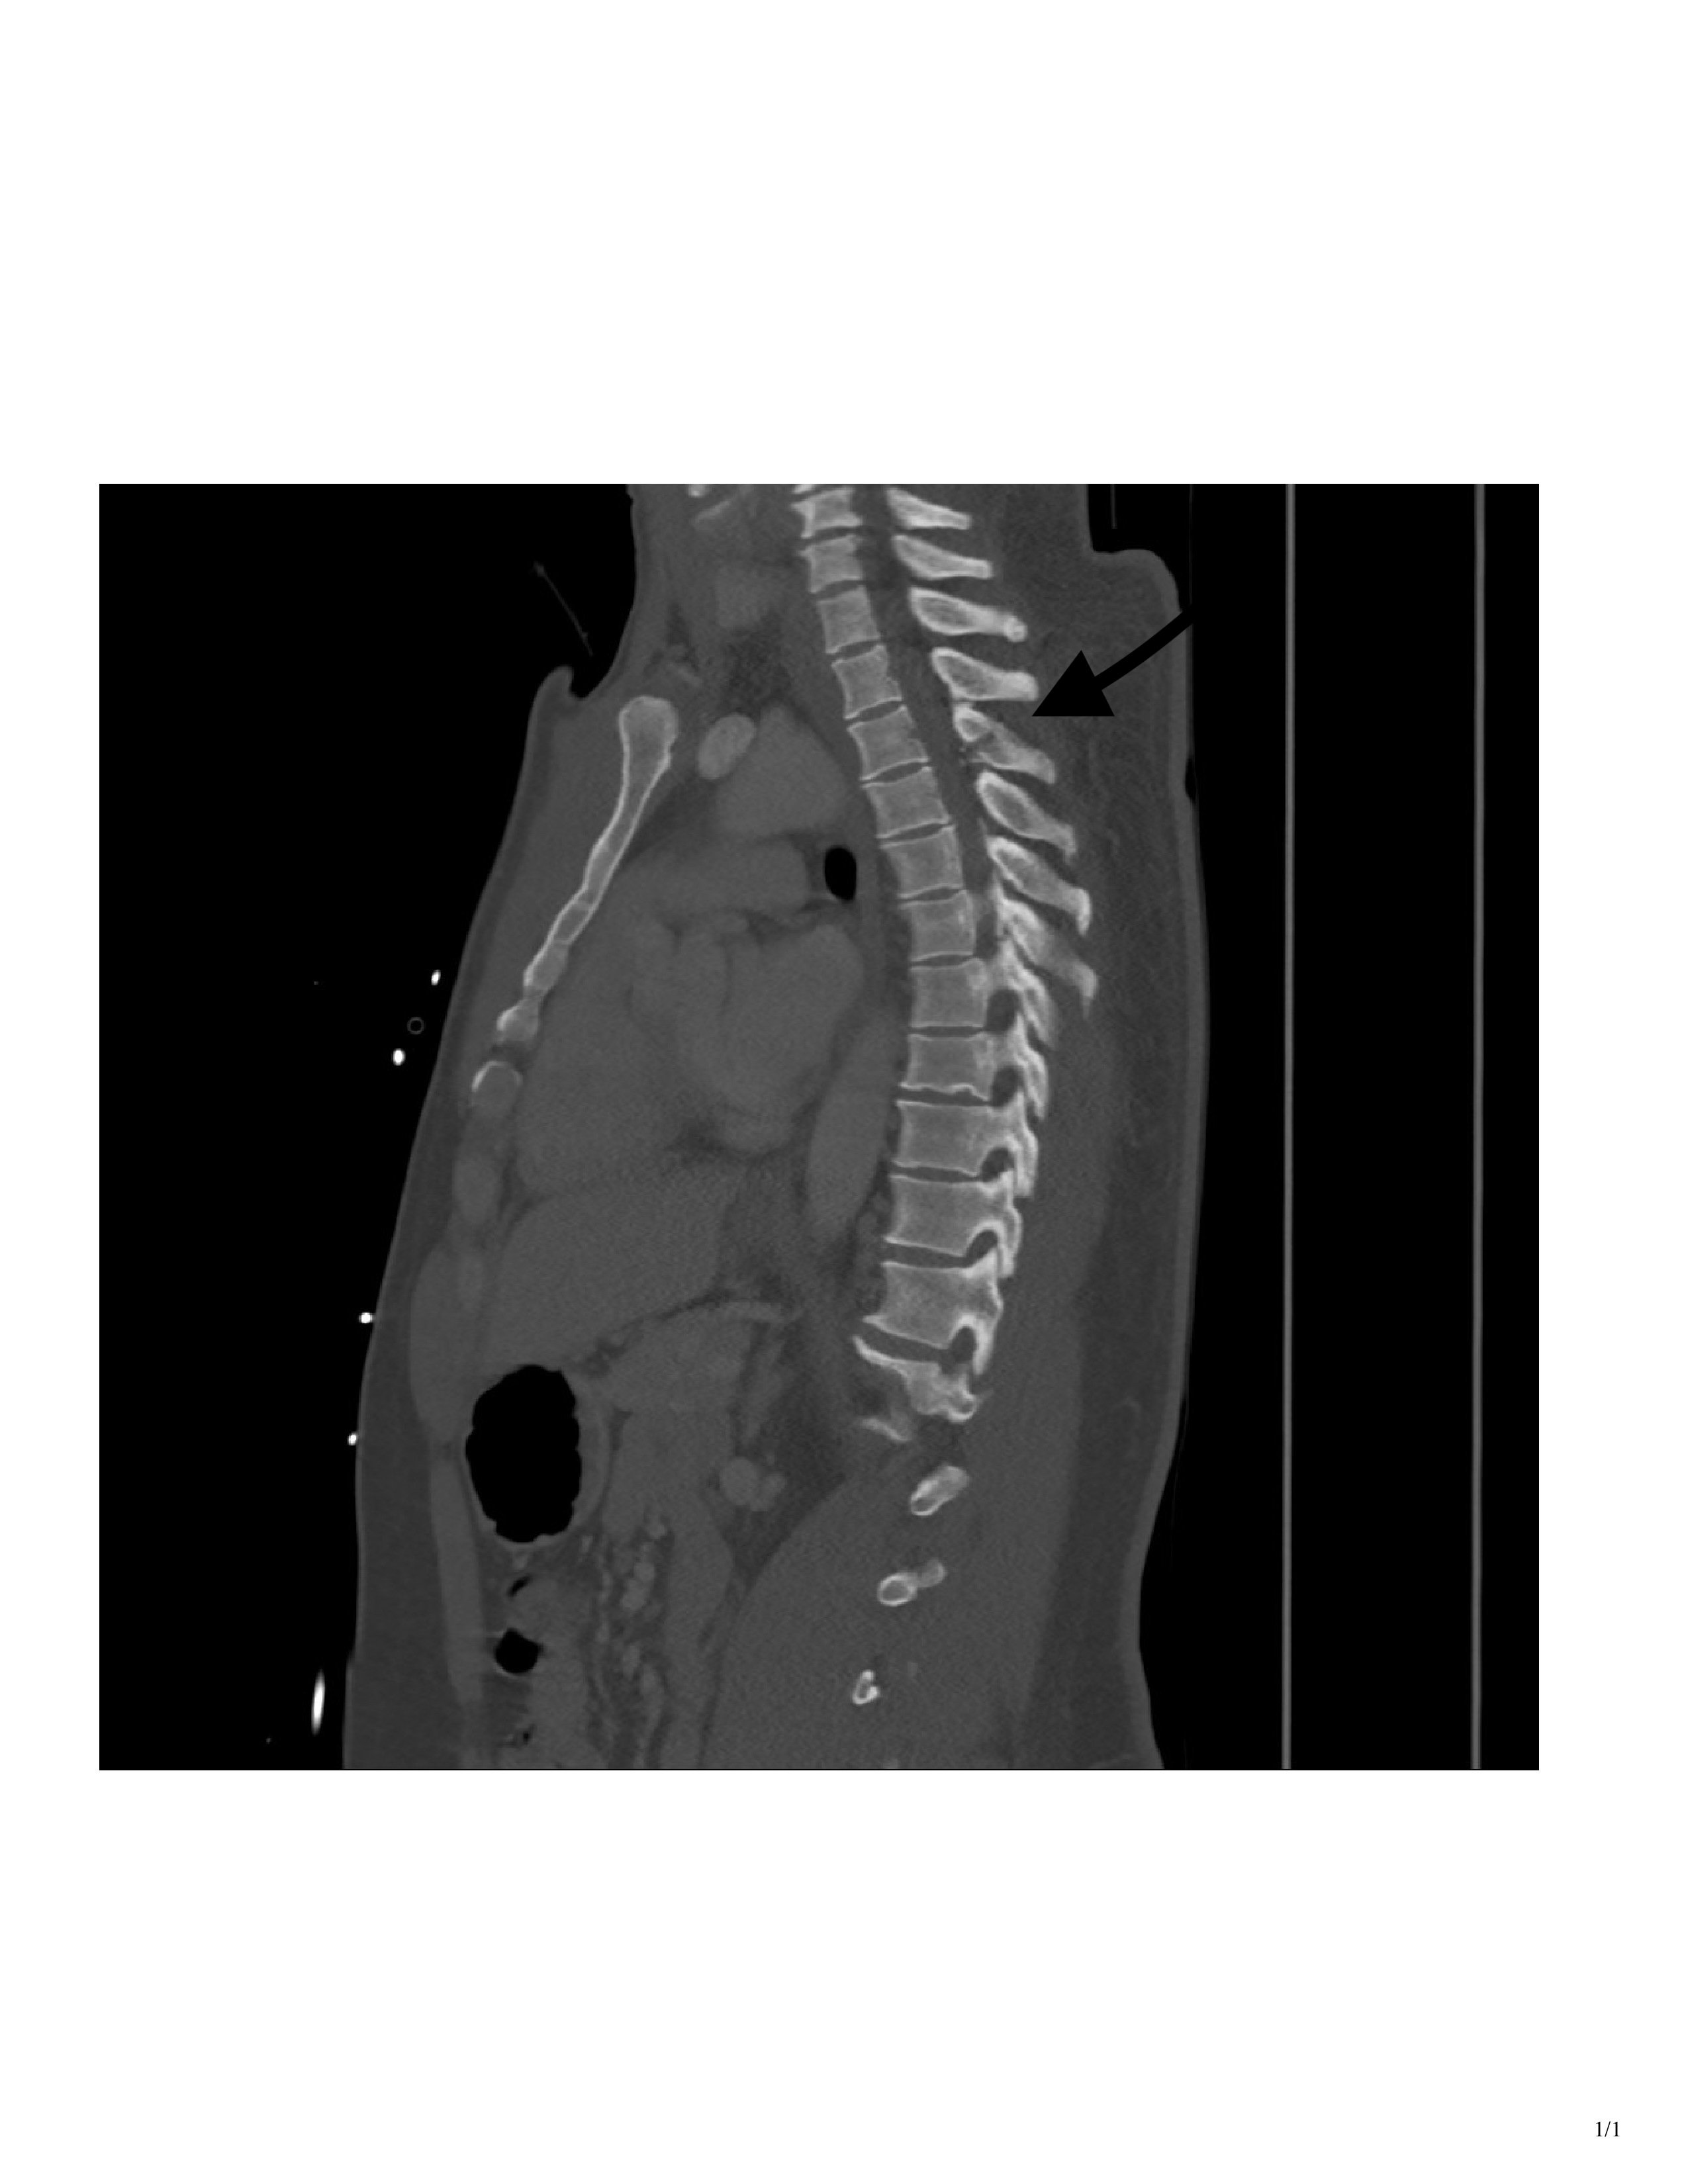

CT imaging showed a T3 spinous process fracture raising concern for intracanal blood products and possible cord injury. MRI later that night confirmed cord contusion with possible injury to the right hemi cord, and dorsal epidural hematoma extending from T2 to T10.

At the time of presentation, we knew the patient displayed clinical signs of Brown-Séquard, and the CT showed injury on the right side of the cord. What was unclear at the time was whether the patient had a true hemi-section of the spinal cord, leading to permanent disability, or if he was instead suffering from a transitory spinal shock due to swelling and hematoma.

An MRI obtained the next day confirmed right-sided spinal cord hemi-section, as well as associated cord contusion and epidural hematoma. Additionally, when the patient was discharged from the Shock Trauma ICU several days later, he was still exhibiting the same neurological deficits. The patient was discharged directly to a rehabilitation center, where occupational and physical therapists were expected to help him maximize his recovery and learn to live with his new deficits.